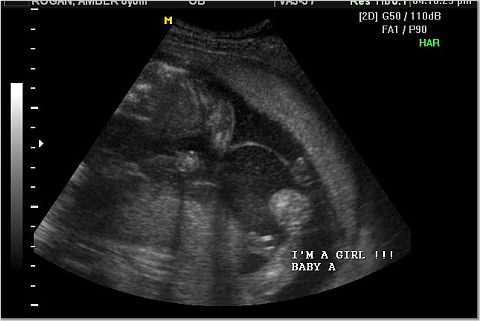

The "It's a girl" shots.

Right above the "I'm" in the first pic and to the left of the "I'm" in the second pic

are the 3 white lines that indicate girl.